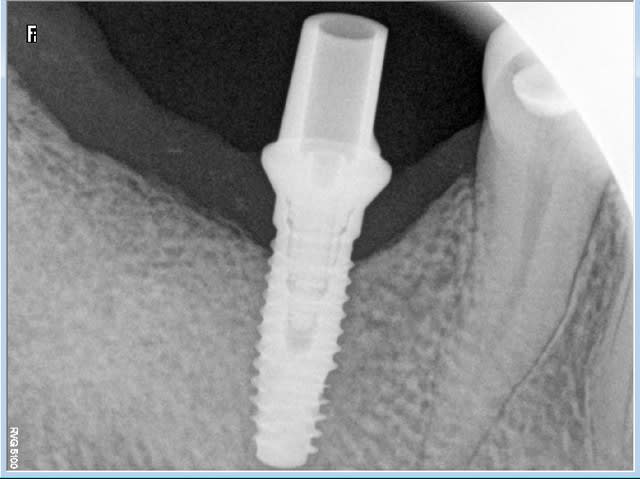

L'implant, un Biomet 3i 4,3mm a été posé en 46 par mon correspondant.

Avec le pilier droit, l'articulé serait en bout à bout avec 16 et distalé par rapport à la 45. Si je veux le point de contact, un grand porte à faux est necessaire.

Pour ce faire, il est possible d'utiliser un pilier angulé 15° qui mesialerait la couronne et retablirait un bon engrènement.

Le hic, selon moi, compte tenu du type morpho du patient est la transmission des forces de mastication avec risque de fracture de l'implant. Et ce d'autant plus qu'il y a une petite cratérisation et que par conséquent l'implant n'est pas entièrement enfoui.

le poseur aurait du penser à la prothèse avant de poser, et l'implant n'aurait il pas du être un peu plus profond?